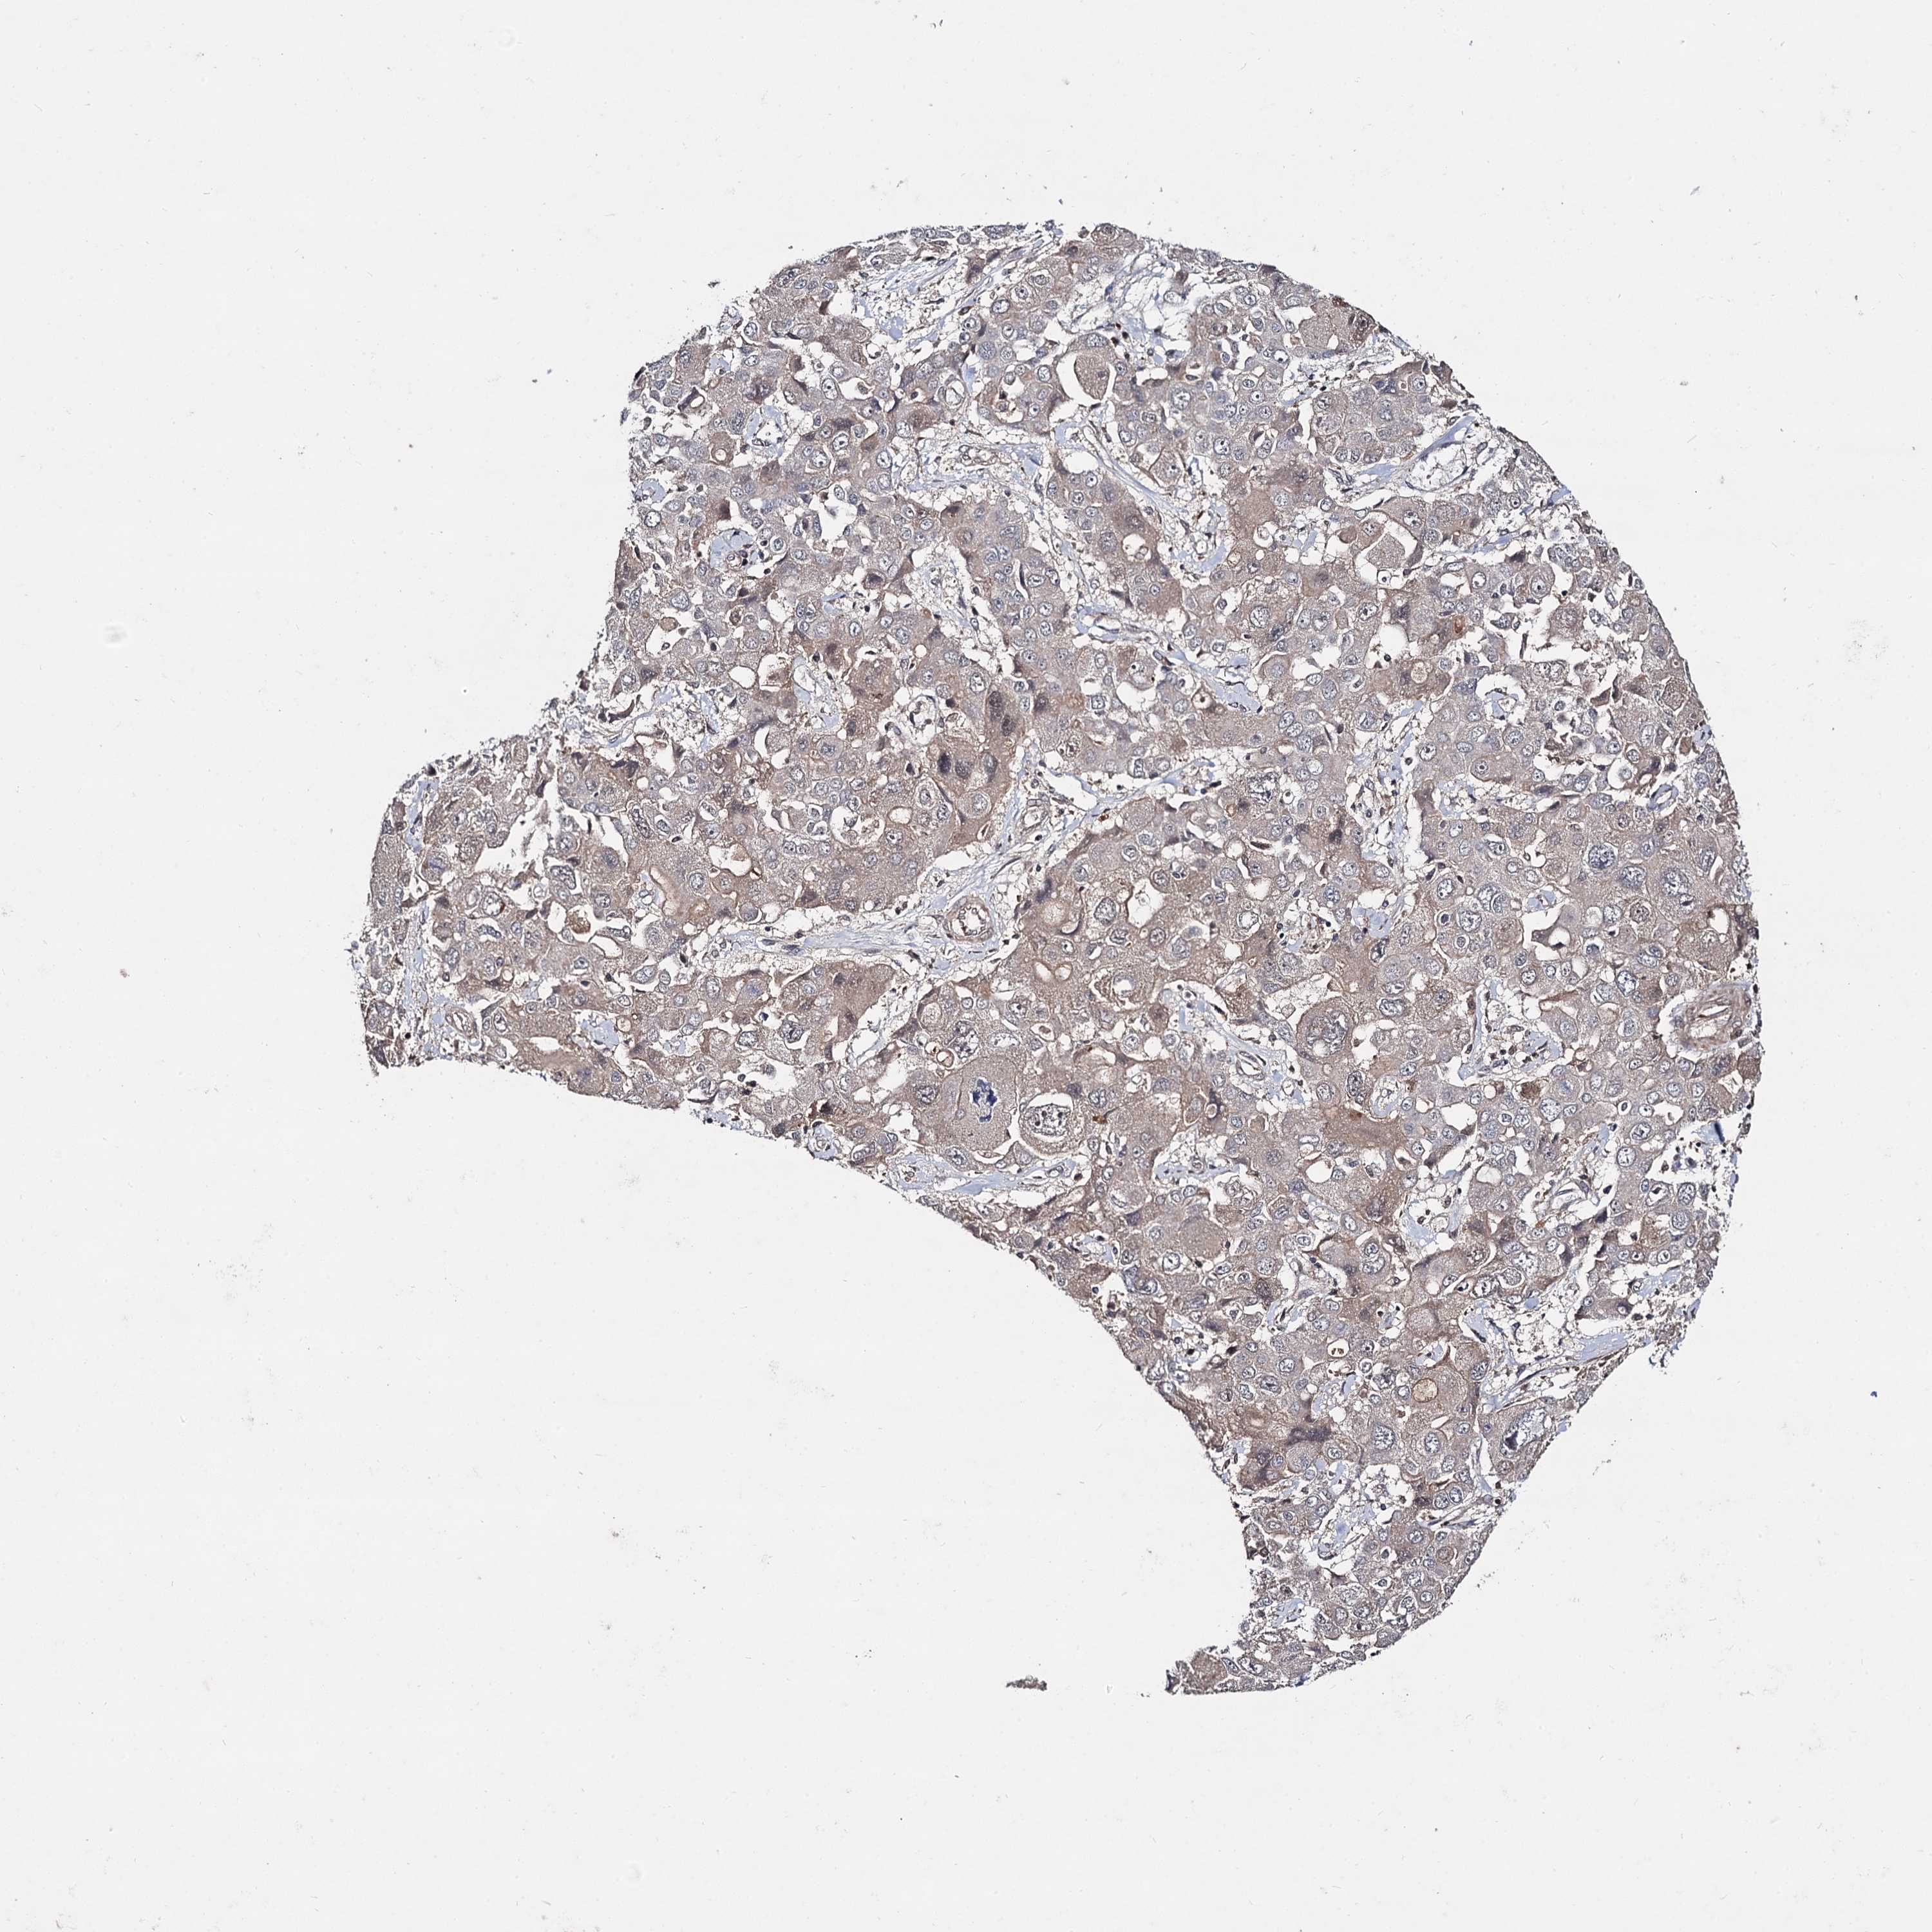

LIVER CANCER - Protein expressioni

A mouse-over function shows sample information and annotation data. Click on an image to view it in a full screen mode. Samples can be filtered based on level of antibody staining by selecting one or several of the following categories: high, medium, low and not detected. The assay and annotation is described here.

Note that samples used for immunohistochemistry by the Human Protein Atlas do not correspond to samples in the TCGA dataset.

Antibody stainingi

Antibody staining in the annotated cell types in the current human tissue is reported as not detected, low, medium, or high, based on conventional immunohistochemistry profiling in selected tissues. This score is based on the combination of the staining intensity and fraction of stained cells.

Each image is clickable and will lead to virtual microscopy that enables deeper exploration of all samples and also displays staining intensity scores, fraction scores and subcellular localization as well as patient and tissue information for each sample.

Cholangiocarcinoma

Carcinoma, Hepatocellular, NOS